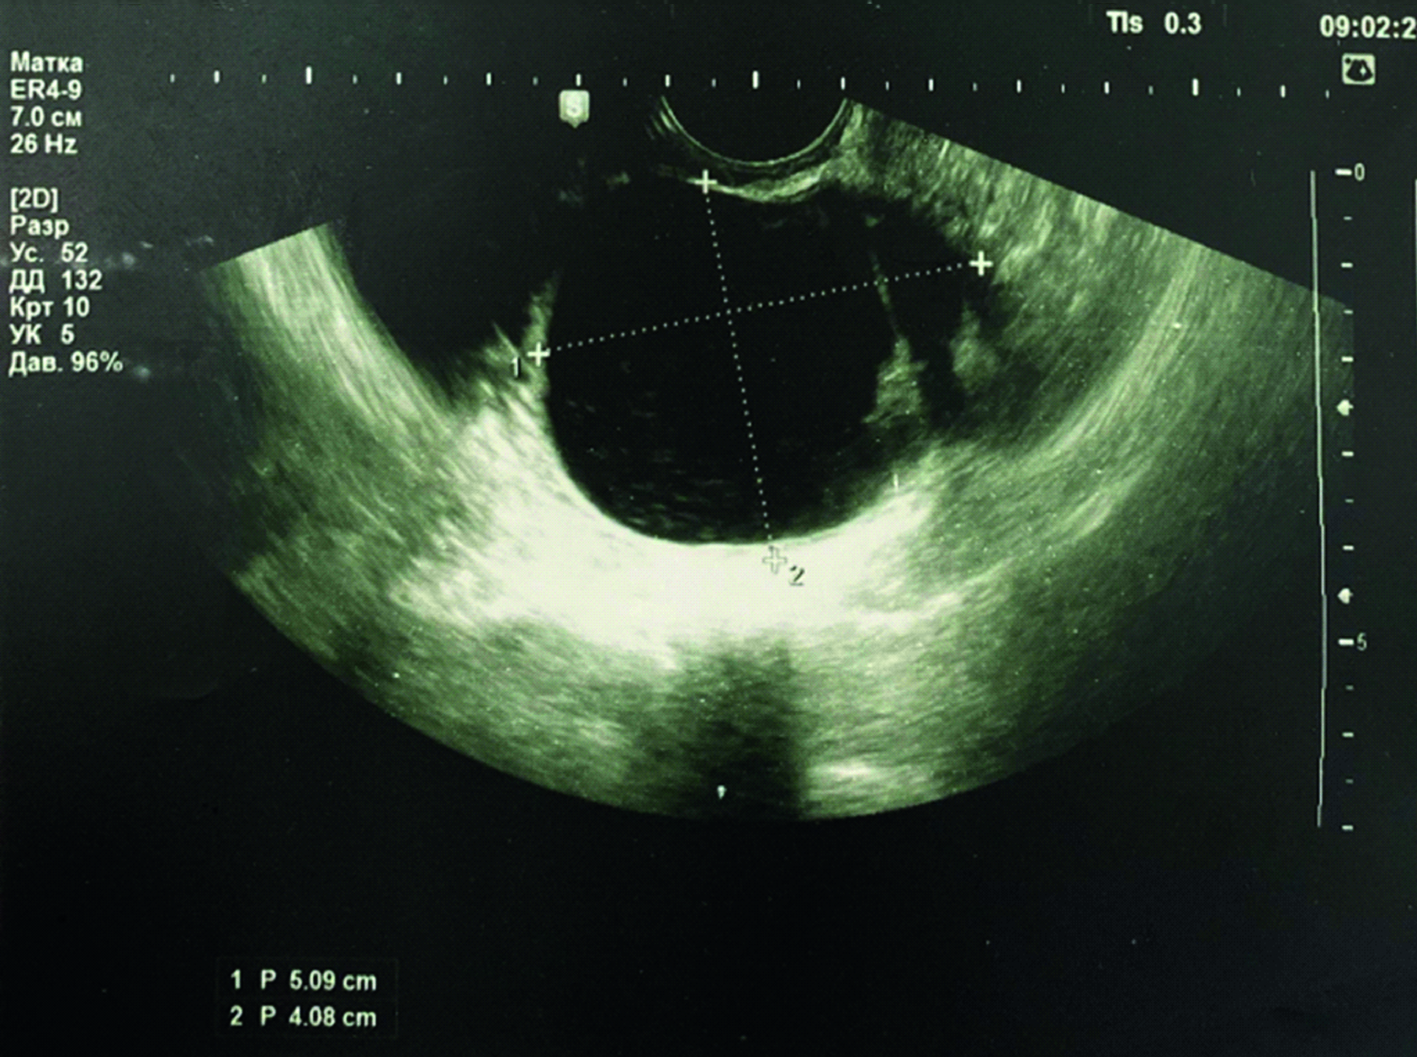

Больная К., 32 года, поступила в отделение онкогинекологии (июнь, 2015 г.) ГАУЗ Республиканского клинического онкологического диспансера Минздрава Республики Татарстан (РКОД МЗ РТ) после ежегодного медицинского осмотра на рабочем месте, где эхографически было выявлено подозрительное новообразование в проекции правого яичника. УЗИ, выполненное в РКОД МЗ РТ, выявило кистозную массу с гипер- эхогенными включениями в правом яичнике размером 50,9×40,8 мм, а также свободную жидкость в брюшной полости (рисунок 1).

Рисунок 1. Ультразвуковое изображение пациентки с подозрением на рак правого яичника.